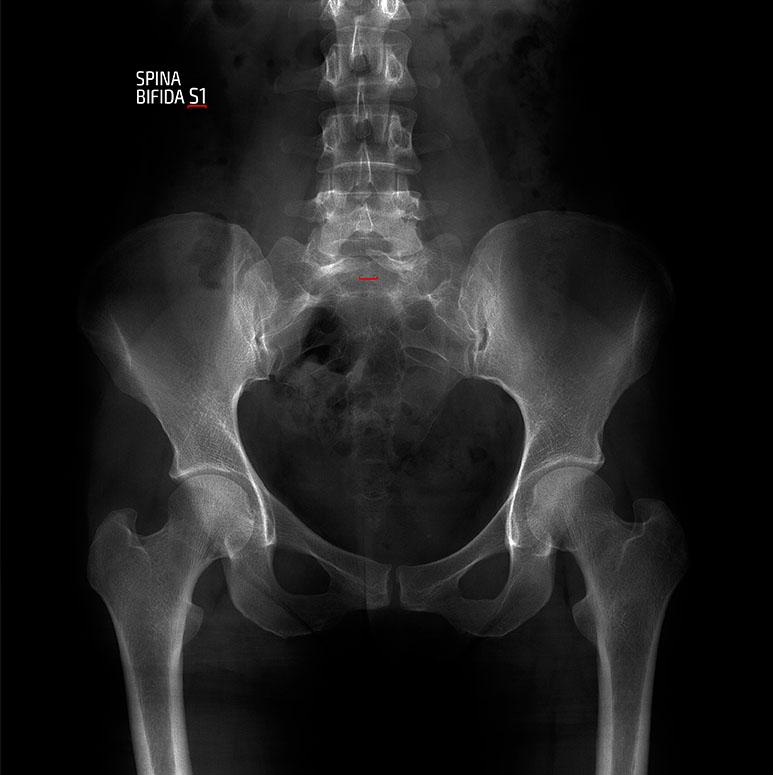

El terme defectes del tub neural (DTN) o espina bífida inclou un grup divers de malformacions congènites del sistema nerviós central que afecten predominantment la medul·la espinal i la columna vertebral. En els casos més greus com la mielomeningocele i la meningocele, hi ha una manca de tancament de la columna vertebral que permet que la medul·la espinal surti a l’exterior (defectes oberts) i els més lleus com els lipomes o lipomielomeningocele es manifesten com una tumoració tova coberta de pell, com una zona lumbar pilosa o poden passar desapercebuts (defectes tancats). Els defectes més greus es poden associar a altres malformacions cerebrals (malformació de Chiari II).